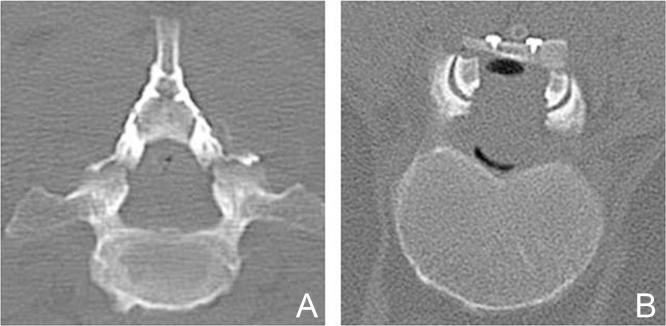

Surgery for spinal intramedullary tumors remains one of the major challenges for neurosurgeons, due to their relative infrequency, unknown natural history, and surgical difficulty. We are sure that safe and precise resection of spinal intramedullary tumors, particularly encapsulated benign tumors, can result in acceptable or satisfactory postoperative outcomes. General surgical concepts and strategies, technical consideration, and functional outcomes after surgery are discussed with illustrative cases of spinal intramedullary benign tumors such as ependymoma, cavernous malformation, and hemangioblastoma. Selection of a posterior median sulcus, posterolateral sulcus, or direct transpial approach was determined based on the preoperative imaging diagnosis and careful inspection of the spinal cord surface. Tumor-cord interface was meticulously delineated in cases of benign encapsulated tumors. Our retrospective functional analysis of 24 consecutive cases of spinal intramedullary ependymoma followed for at least 6 months postoperatively demonstrated a mean grade on the modified McCormick functional schema of 1.8 before surgery, deteriorating significantly to 2.6 early after surgery (< 1 month after surgery), and finally returning to 1.7 in the late postoperative period (> 6 months after surgery). The risk of functional deterioration after surgery should be taken into serious consideration. Functional deterioration after surgery, including neuropathic pain even long after surgery, significantly affects patient quality of life. Better balance between tumor control and functional preservation can be achieved not only by the surgical technique or expertise, but also by intraoperative neurophysiological monitoring, vascular image guidance, and postoperative supportive care. Quality of life after surgery should inarguably be given top priority.

由于脊髓髓内肿瘤相对少见、自然病史不明且手术难度大,其手术治疗仍是神经外科医生面临的主要挑战之一。我们确信,安全、精确地切除脊髓髓内肿瘤,尤其是包膜完整的良性肿瘤,可带来可接受或令人满意的术后结果。本文通过室管膜瘤、海绵状血管畸形和血管母细胞瘤等脊髓髓内良性肿瘤的实例,探讨了一般手术概念与策略、技术考量以及术后功能结果。根据术前影像诊断和对脊髓表面的仔细检查,决定选择后正中沟、后外侧沟或经皮质直接入路。对于包膜完整的良性肿瘤,要仔细勾勒肿瘤与脊髓的界面。我们对24例连续的脊髓髓内室管膜瘤患者进行了回顾性功能分析,这些患者术后至少随访6个月,结果显示术前改良麦考密克功能量表平均评分为1.8,术后早期(术后<1个月)显著恶化至2.6,术后晚期(术后>6个月)最终恢复至1.7。术后功能恶化的风险应予以认真考虑。术后功能恶化,包括术后很长时间仍存在的神经性疼痛,会显著影响患者的生活质量。不仅通过手术技术或专业知识,还通过术中神经生理监测、血管影像引导和术后支持治疗,可在肿瘤控制和功能保留之间实现更好的平衡。术后生活质量无疑应被置于首位。